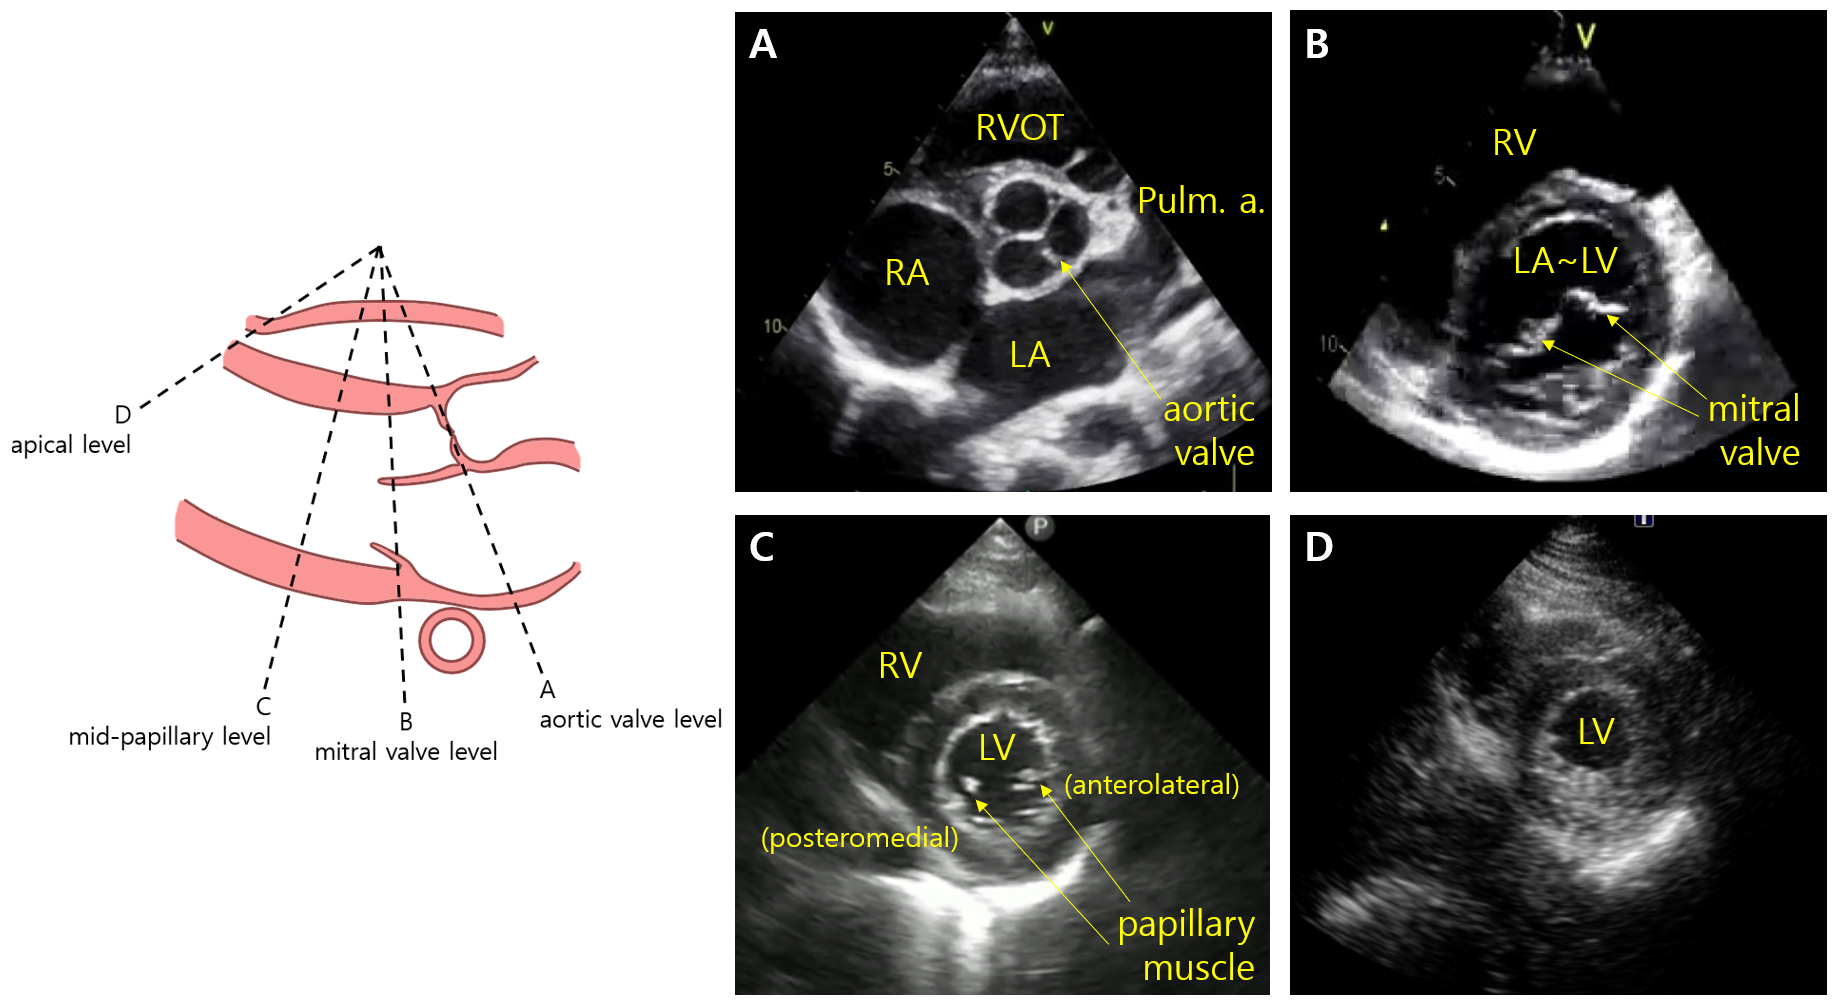

3) Parasternal short axis

(1) Probe: Parasternal long axis에서 probe를 약 90o(70~110o) 시계방향으로 회전

(2) 구조물: Probe를 기울여 아래 A~D 중 어느 level을 잡느냐에 따라 볼 수 있는 구조물이 달라짐

Level

구조물

평가

Aortic valve

RA, RV(RVOT), LA, pulmonary artery, AV/TV

AV 형태

*TV 형태, 역류 여부

*PDA 존재 여부

Mitral valve

LV, RV, MV

MV 형태, 면적

LV의 EF, RWMA

D-shaped LV의 유무

Mid-papillary

LV, RV, MV의 papillary muscles

Apical

LV, RV

LV의 RWMA

* Aortic valve level에서 조금 각도를 틀면 tricuspid valve, PDA(있을 경우) 등이 보이기 때문에 TR, PDA 등을 평가할 수 있다.